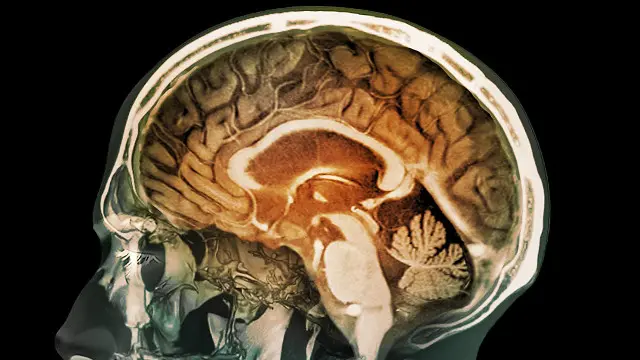

درد کی دوا کا تجربہ: 90 میں سے ایک شخص کا ’دماغ مردہ‘

فرانس میں درد کی ایک نئی دوا کے تجرباتی استعمال نے ایک شخص کے دماغ کو مردہ کردیا ہے تاہم دواساز کمپنی کا اصرار ہے کہ اس نے تمام بین الاقوامی ضابطوں کو مدِنظر رکھا تھا۔

ان کا کہنا ہے کہ ہسپتال میں زیرِ علاج پانچ میں سے تین مریضوں کے دماغ نے کام کرنا چھوڑ دیا ہے۔